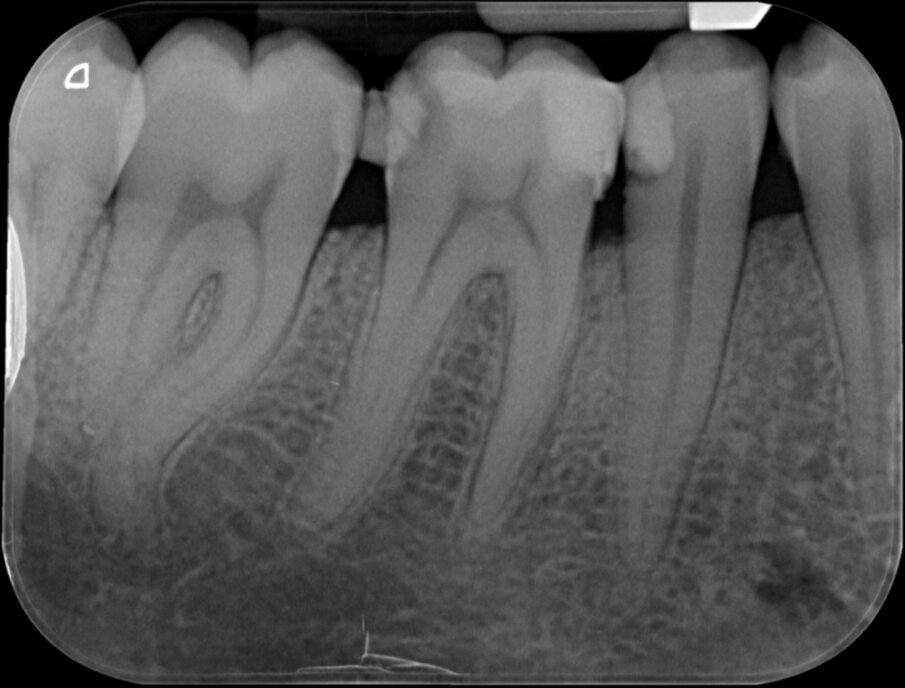

Vier jaar geleden meldde zich een patiënt in onze praktijk met heftige pijn in de regio 46. Na een blik op de bitewing en op de apicale röntgenopname (afbeelding 1 en 2) is de indicatie endodontische behandeling 46 snel gesteld.

De lengte van de kanalen was ongeveer 25 millimeter. Na openen en toegang verkregen te hebben tot het bovenste 2/3 gedeelte van de radix werd het apicale deel van de kanalen benaderd met behulp van SS K-vijlen 08 en 10. We maakten de kanalen doorgankelijk (‘patent’, een term van professor Herbert Schilder) en maakten het kanaal zodanig glad dat we een nieuwe rechte K-vijl zonder te manoeuvreren moeiteloos op de door de elektronische lengtemeter vastgestelde lengte kunnen laten glijden.

Dan zijn we klaar voor het introduceren van WaveOne Gold Primary. Volgens de fabrikant Dentsply kan in het merendeel van de gevallen deze vijl gebruikt worden en de kanalen geprepareerd: het 1-vijlconcept.

De eindfoto’s stemmen tot optimisme. Röntgenologisch lijkt voldaan aan al de eisen die Schilder aan de vorm van geprepareerde kanalen stelde.